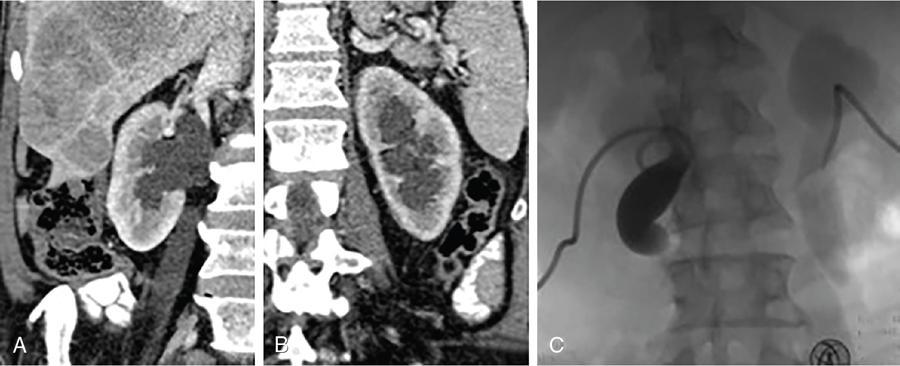

NONVASCULAR RENAL INTERVENTION Amitha Vikrama Nonvascular renal interventions have come a long way and have significantly reduced the surgical mortality and morbidity. It also paves way for short hospital stay and thus reducing the chances of nosocomial infection. They are usually pinhole or keyhole procedures with less distortion of the anatomy and physiology. They vary from image-guided aspiration/biopsy to percutaneous nephrostomy to complex procedures like ureteric stenting, strictureplasty, percutaneous nephrolithotomy etc. Iversen and Brun were the first to perform percutaneous renal biopsy of native kidneys in 1951. Over the years, newer imaging and biopsy techniques have evolved which have increased the biopsy yield to >95% and significantly reduced the complications of renal biopsy, resulting in decreased mortality rates from 0.12% to 0.02% during the last 50 years NOTE: Solitary renal mass lesions suspicious for malignancy should not be subjected to percutaneous biopsy, as there are chances of tumour seeding along the biopsy track. Excision biopsy is preferred for those lesions as it can be curative. USG-guided renal biopsy is the preferred method over blind biopsies. It avoids nontarget biopsies and reduces bleeding risks. Usually the lower pole of the kidneys is preferred site in native renal biopsy. The needle has to be directed into the lower cortex and care taken to avoid renal medulla and collecting system. 18G trucut biopsy needles are usually used in adults. In paediatric population, 20G can be used. Rarely, Coaxial technique is used in very obese patients and in those who are unable to lie prone. It is usually done as an inpatient procedure. Four hours of fasting is required to prevent aspiration of gastric contents during the procedure. Antiplatelets and anticoagulants are stopped at least 3–5 days prior. Informed written consent has to be taken after explaining the risks and benefits of the procedure. Patient is to be positioned in prone and USG-guided marking of the site of biopsy done prior to cleaning and draping. The depth of the renal cortex from the skin surface has to be noted. If the ribs are coming in line with the lower pole cortex, then a cranially angulated path is preferred. After infiltration of 2% lignocaine, the biopsy needle is advanced up to and not into the lower pole cortex. As the kidney keeps moving with respiration, the biopsy should be properly timed to avoid hitting the collecting system and medulla. This method is real-time ultrasound guided renal biopsy (Fig. 10.21.1.1). There is another method practiced in few of the institutes where the location of lower pole of the kidney is marked on the skin after ultrasound screening. The marking corresponds to the lower most renal cortex at the end of normal inspiration and the biopsy path will be perpendicular to the bed without any craniocaudal or mediolateral angulation. The distance between the skin and the renal cortex is measured. The patient will be instructed strictly not to change his position. Then the biopsy will be done blindly without any real time USG guidance. With this method, more number of patients can be biopsied in a short interval time. In a transplanted kidney, which is usually grafted in the iliac fossa, biopsy can be obtained from upper or lower pole. Points to remember: Cortical tangential and cortical non tangential approaches have been described (Fig. 10.21.1.2). Cortical tangential approach is described to have better diagnostic yield with lesser complications. In this approach, the needle track will be almost parallel to the capsule so that only the cortical tissue is targeted (Fig. 10.21.1.3A–C). Renal biopsy can also be done with coaxial technique. In this method, a coaxial needle, one size bigger than the biopsy needle, usually 17G, is inserted up to the renal capsule. The stylet is then removed and the 18G biopsy needle is inserted through the coaxial needle and the required number of biopsy specimens obtained. After this, the rent in the capsule can be sealed off with gelatine plugs before removing the coaxial needle. This helps in preventing bleeding complications. In patients with high risk of bleeding due to coagulation abnormalities, transjugular renal biopsy can be done in which renal vein is cannulated and biopsy done from within (Fig. 10.21.1.3D–F). In obese patients who cannot lie prone, biopsies are done in lateral or oblique lateral positions under CT or USG guidance. CT guidance is especially helpful when the visualization of the kidney is difficult on ultrasound. In these cases, coaxial technique is always helpful. In 2019, KHA-CARI guidelines were first published for renal biopsy. A few of the salient recommendations are given below: It is an image-guided procedure in which the renal pelvicalyceal system is accessed percutaneously which is predominantly used for decompressing an obstructed system and also for various other therapeutic procedures. It is usually done under local anaesthesia and IV sedation. Major procedures might require general anaesthesia. All routine preprocedural blood tests and coagulation profile should be done. Appropriate antibiotics are administered intravenously prior to the procedure. 21G needle, 018 and 035 wires, appropriate dilators, sheath and pigtail drainage catheter. Ultrasound and fluoroscopy is required for guidance. Patient is usually positioned prone on the table. Under special circumstances, lateral or oblique positions are also used. After instillation of local anaesthesia, a 21G needle is used to access the renal calyx under USG guidance. Once the urine flow is seen, nonionic contrast is injected to delineate the renal collecting system. A 018 wire is passed through the needle into the pelvicalyceal system and later exchanged for a 035 wire. Appropriate tissue dilators are used to dilate the track before placing a pigtail drainage catheter. The drain is secured by stay sutures and connected to a urobag. The initial urine sample is to be sent for culture and sensitivity (Figs. 10.21.1.4–10.21.1.6). Ureteric stenting was first described by Zimskind et al endotracheal tube al in 1967. It is one of the commonest procedure done in urology practice It is usually done after doing a percutaneous nephrostomy. The percutaneous nephrostomy (PCN) drain is replaced with a 6F or 8F sheath over a guidewire and ureterogram is obtained to assess the site of stricture or obstruction. Using a catheter and guide wire combination, the stricture is negotiated and the exchange length hydrophilic wire is parked in the bladder. The ureteric length is measured and appropriate-sized double J (DJ) stent is inserted over the wire. Care is taken to get the loops formed at both ends of the DJ stent so that stent migration is prevented (Fig. 10.21.1.7). A variety of delivery systems are available for the deployment of the ureteric stent exist: pusher mechanism, string release and sheath (similar to an inferior vena cava (IVC) filter). Post stent insertion, the nephrostomy drain can be retained for a couple of days. The drain is closed externally and USG screening is done the next day to confirm antegrade flow after which the drain can be removed.